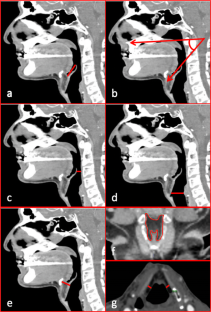

All adult male patients who underwent head and neck CTAs between 2011 and 2018 were initially included and categorized according to their BMI: (1) BMI < 20; (2) 20 ≤ BMI < 25; (3) 25 ≤ BMI < 30; (4) 30 ≤ BMI < 35; and (5) BMI ≥ 35. Anatomical measurements included pre-epiglottic and paraglottic fat-pad dimensions, airway width at the epiglottis tip and base, and epiglottis angle. For statistical analysis, BMI was regarded both as a categorical and continuous variable.

One hundred and five scans were included. BMI ranged from 15.90 to 44.40 kg/m2. Significant differences were found in pre-epiglottic and paraglottic fat measurements between BMI subgroups 1–5 (Pre-epiglottic fat depth: 17.75, 17.74, 19.04, 20.73, and 21.09 mm, respectively, P = 0.005, correlation 0.343, and P < 0.001 in continuous measurement; Paraglottic space average width: 3.5, 5.4, 5.46, 6.85, and 7.38 mm, P < 0.001, correlation 0.532, and P < 0.001 in continuous measurement). As BMI increased, the epiglottis-hard-palate angle increased (56.4°, 55.3°, 65.2°, 64°, and 68.4°, P = 0.001, correlation 0.354, and P < 0.001 in continuous measurement). No significant difference was found in airway width between subgroups at the epiglottis tip or base. Yet, in continuous variables analysis, a significant negative correlation was found between BMI scores and the airway width at the epiglottis base (−0.226, P = 0.02).